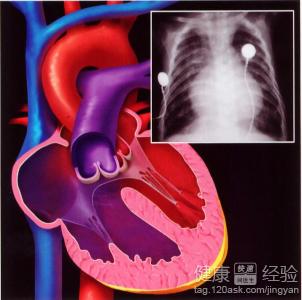

先天性心髒病手術後注意事項